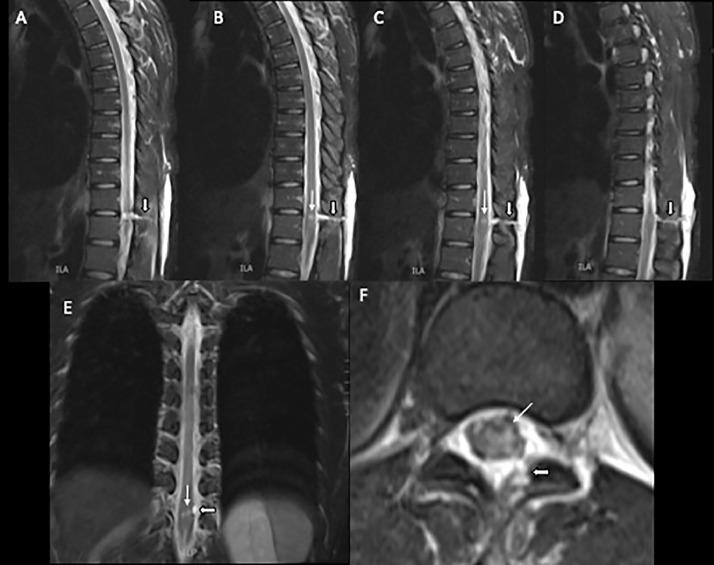

Brown-Sequard Syndrome is a neurologic disorder caused by partial spinal cord injury and disruption of the corticospinal tract, dorsal columns, and spinothalamic tract. We present a 32-year-old male with partial T11-12 cord transection due to a penetrating knife injury. In addition to the classical neurological symptoms of Brown-Sequard Syndrome, he also exhibited ipsilateral peripheral vasodilatation below the level of injury. This finding is attributed to the disruption of the intermediolateral columns of the spinal cord and impaired sympathetic tone on the peripheral vasculature. Awareness of this finding can raise the radiologist's suspicion for spinal cord injury in the setting of trauma and peripheral vasodilation.